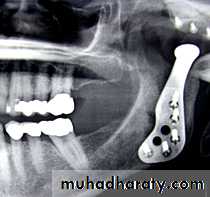

Interpositional Arthroplasty

To prevent re-ankylosis, interposition of alloplastic or autogenous graft is placed between the cut ends of the joint.Temporalis Muscle and Fascia

Full Thickness Skin Graft

Alloplastic Materials like silicon

Once the gap arthroplasty has been accomplished, the alloplastic material is molded to the right size and secured into position before closure of the surgical site.